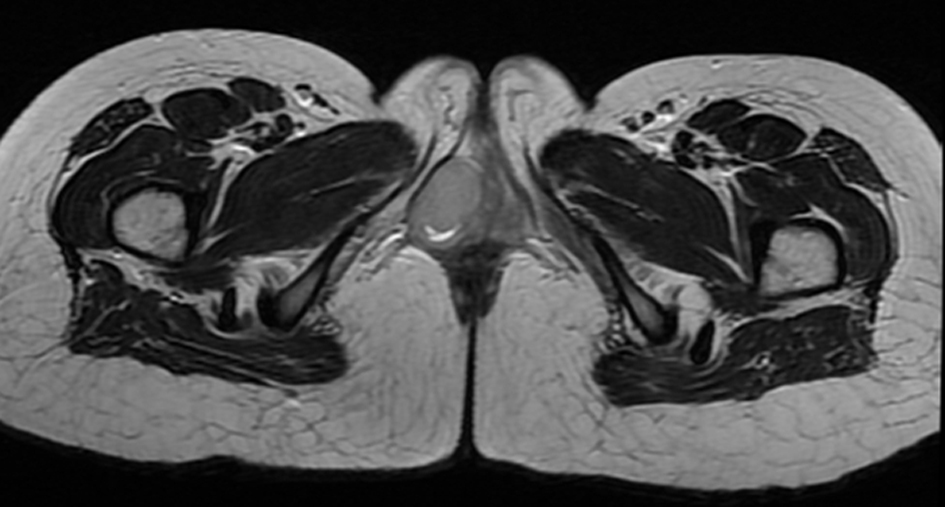

A 17-year-old girl presented with swelling at the clitorial region of few weeks duration. On examination, there was a swelling 3 × 2 × 2 cm at the clitorius. Computerized tomography (CT) scan of the abdomen and pelvis showed a right ovarian cyst of 3.5 × 2.5 cm in addition to the clitorial mass. She underwent diagnostic laparoscopy and left ovariectomy for the ovarian lesion and excision of the clitorial mass at the local hospital and was subsequently referred to us. Her performance status was 0, blood and serum chemistries were normal and lactate dehydrogenase was 405 U/L. The histopathological examination of the specimen from clitoris showed a neoplasm composed of round cells in large lobules separated by fibrocollagenous stroma, cells with scanty to moderate cytoplasm and vesicular nuclei, and many thin walled blood vessels were seen (Fig. 1). The tumor cells were strongly positive for MIC2, positive for neuron-specific enolase and negative for desmin, cytokeratin, myogenin and synaptophysin (Fig. 2). This was diagnostic of PNET/ES. The ovarian lesion was non-malignant. She was started on chemotherapy with vincristine, adriamycin, cyclophosphamide alternating with ifosphamide and etoposide and received local radiation 45 Gy/20# at ninth to 12th weeks. She achieved complete remission and chemotherapy was continued for 1 year. However, 4 months after treatment completion, she developed local recurrence in the form of well-defined mass 2 × 2 cm at the mons pubis. MRI showed multiple vulval deposits, deposits in the lower anterior pelvic wall, bilateral iliac bone, sacrum and femur (Fig. 3, 4). Bone scan showed multiple bone deposits and CT scan of chest showed multiple lung metastasis. She was given only supportive care and she died 6 months later.

![]() Click for large image | Figure 4. MRI axial T2WI-lesion appears hyperintense. |